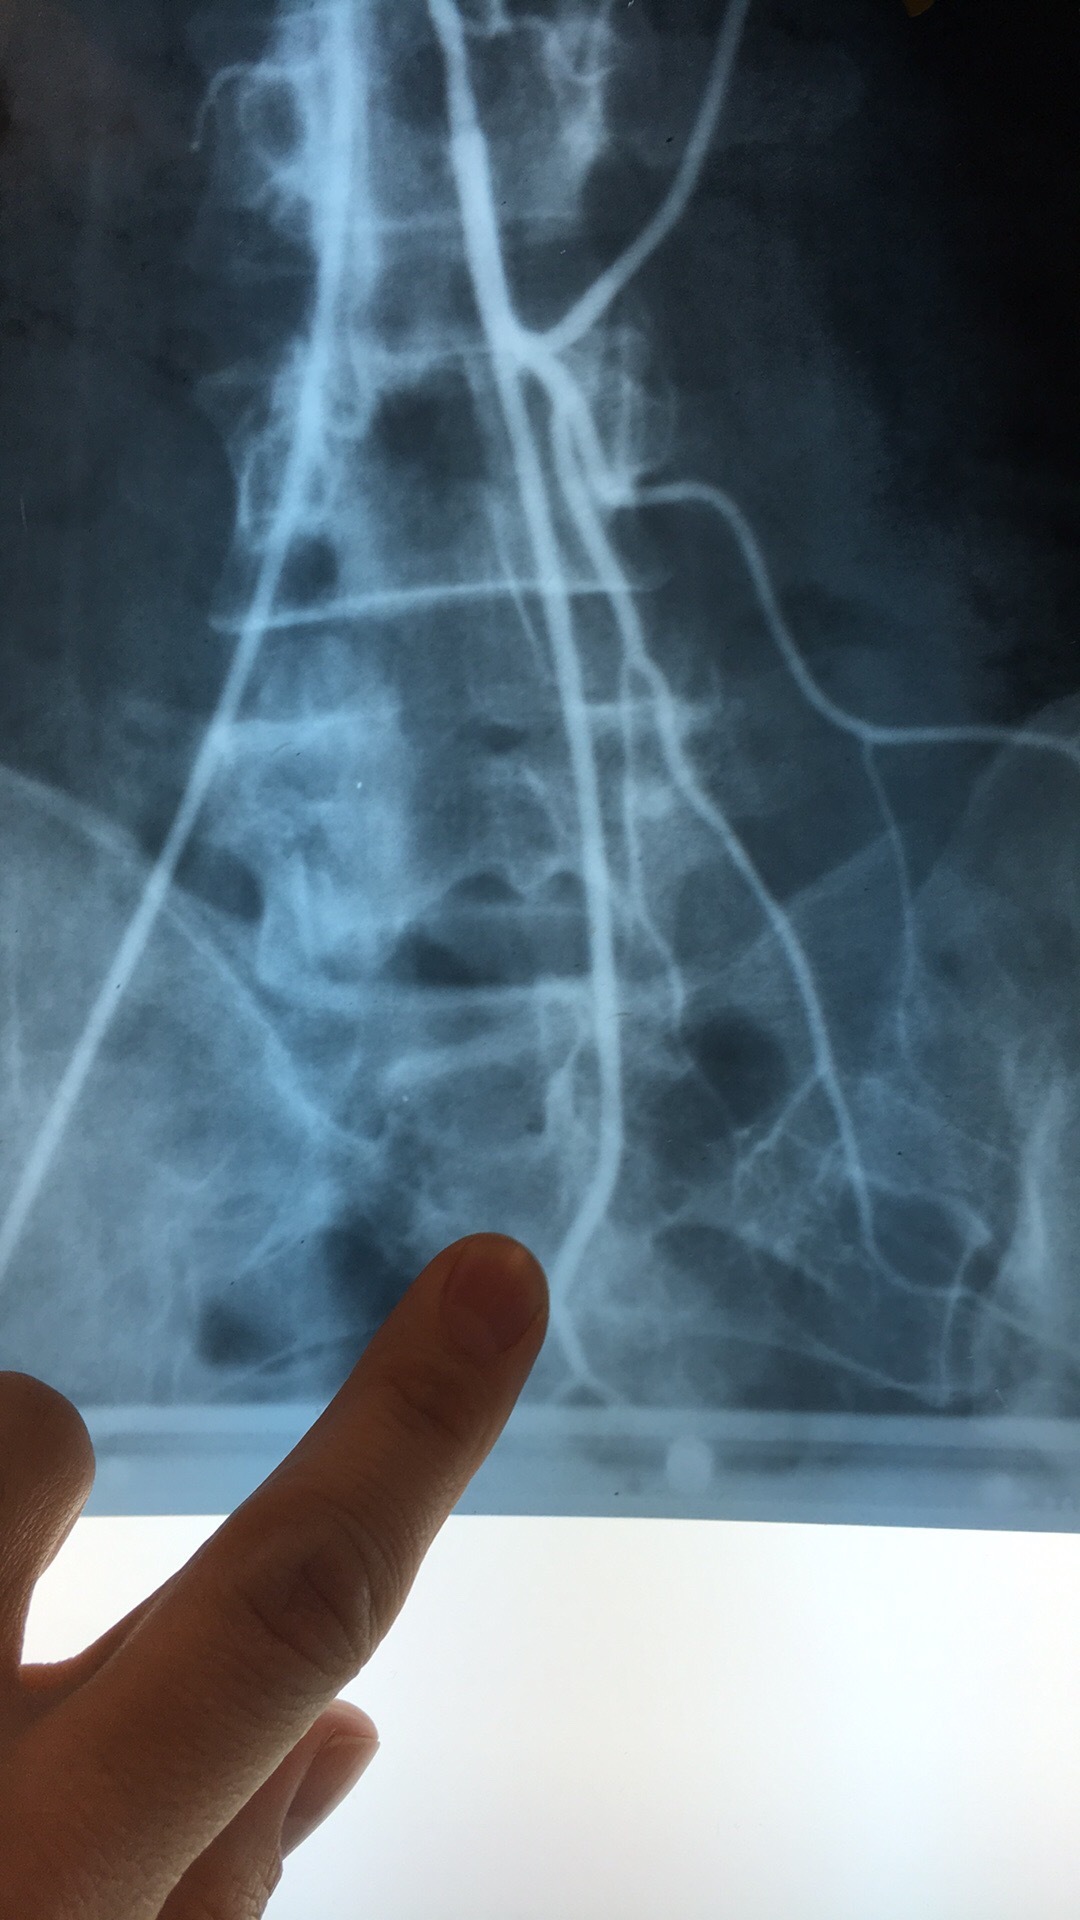

Which artery? What are the 5 branches?

Superior Mesenteric Artery. Intestinal Arteries, Right Colic Art, Middle Colic Art, Ileocolic Art, Inferior Pancreaticoduodenal Art